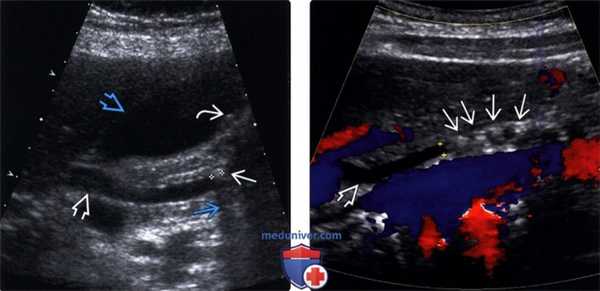

(Левый) На продольном УЗ срезе в общем желчном протоке определяется единичный эхо-генный очаг, отбрасывающий плотную акустическую тень, что соответствует картине конкремента. Общий желчный проток слегка расширен, вероятно, вследствие вызванной конкрементом обструкции.

(Правый) На поперечном косом УЗ срезе у этого же пациента подтверждается наличие конкремента в просвете общего желчного протока. Позади конкремента видна акустическая тень.

(Левый) У того же пациента на продольном УЗ срезе в просвете желчного пузыря определяется несколько конкрементов. Эхо-генные конкременты отбрасывают акустическую тень.

(Правый) При рентгеноскопии при эндоскопической ретроградной холанги-опанкреатографии возле дистального конца расширенного общего желчного протока определяется дефект заполнения, что соответствует картине холедохолитиаза. Также произошел рефлюкс контраста в желчный пузырь, где как дефекты заполнения просвета желчного пузыря выявляются множественные конкременты.

(Левый) На продольном УЗ срезе в общем желчном протоке определяется гиперэхогенный конкремент, отбрасывающий плотную тень. В просвете желчного пузыря определяются другие конкременты.

(Правый) В общем желчном протоке определяются несколько конкрементов, вызывающих небольшое расширение внепеченочных желчных протоков. Цветовая допплерография помогает дифференцировать общий желчный проток (в котором отсутствует цветовая индикация) от прилегающих сосудов.